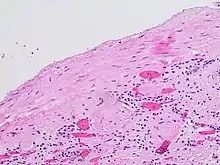

- Mandolin S. Ziadie, M.D. "Simple cysts". Pathology Outlines. Topic Completed: 1 November 2011. Minor changes: 1 October 2019